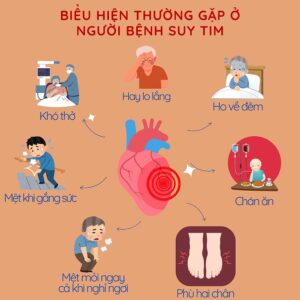

Triệu chứng

- Khó thở.

- Mệt mỏi.

- Sưng chân và mắt cá chân.

- Ho dai dẳng có thể nặng hơn vào ban đêm; có khi ho ra máu hay bọt hồng.

- Thở khò khè.

- Đầy hơi.

- Ăn mất ngon.

- Tăng cân hoặc sụt cân.

- Chóng mặt và ngất xỉu.

- Nhịp tim nhanh, loạn nhịp tim hoặc đánh trống ngực.